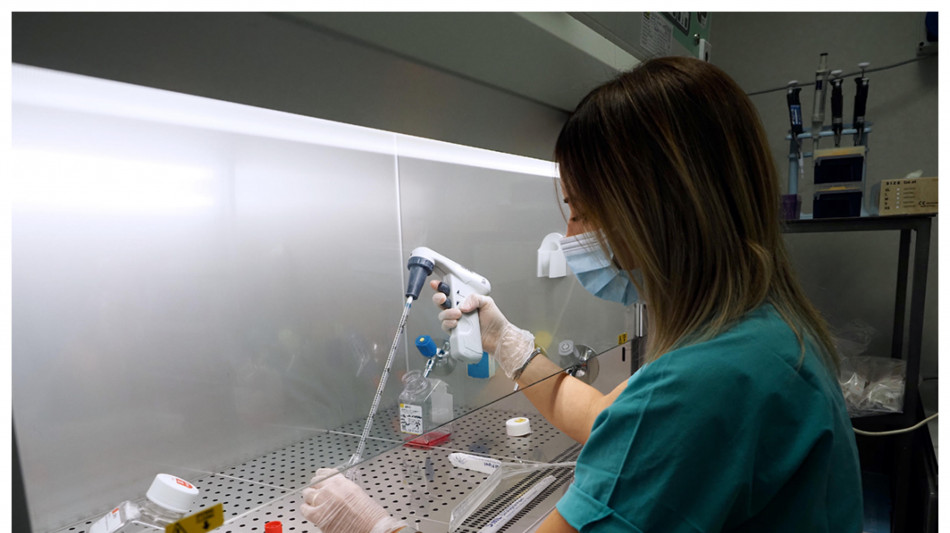

Ottenute cellule staminali del sangue, gemelle di quelle umane

Test su topi, aprono a cure per la leucemia